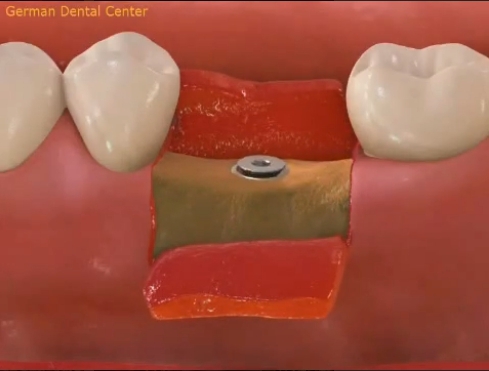

- Имплантация